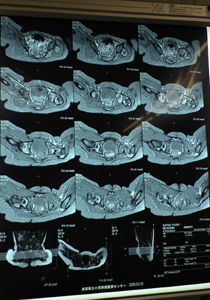

そしてMRI(レントゲンよりももっと詳しくわかるように)を撮りました。これがかなり大変で40分間じっとしていなくてはならないので睡眠剤を使用。しかし途中で起きてしまったので薬を追加。目が覚めた後、薬の副作用なのか泣いて泣いてちょっとパニックになり今までに見た事のない状態でちょっとびっくりしました。あまり薬は使いたくないけどしょうがないのかなぁ…。それでもこの日の夕食は完食し一安心。夜はなかなか寝付けず9時過ぎに疲れ果てて就寝。

ren.2.jpgMRI1.jpg